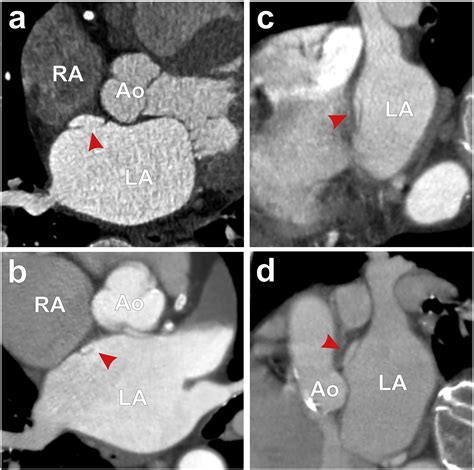

• Atrial Fibrillation: An irregular heartbeat that can cause blood clots to form and travel to the brain.

• Angiography: A procedure to visualize the blood vessels in the brain and detect any blockages or narrowing.